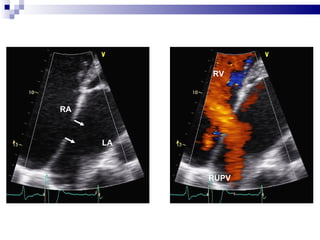

LA RA RUPV RV

Morphology 4 Types of ASD:  * ostium primum * ostium secundum * sinus venosus * coronary sinus defects  ↑ Left to right shunt:  * left ventricular compliance↓  * left atrial pressure  ↑

Intervention Device closure  * For secundum ASD with stretched diameter < 36 mm + adequate rims  * Exception: 1) Anomalous pulmonary venous connection 2) Proximity to the AV valves / coronary sinus / systemic  venous drainage Surgery * For sinus venosus or ostium primum defects or with secundum defects with unsuitable anatomy  * primary suture closure or using a pericardial or synthetic patch

Percutaneous ASD closure Percutaneous closure of an ASD is indicated for the closure of secundum ASDs with a sufficient rim of tissue around the septal defect so that the closure device does not impinge upon the  SVC ,  IVC , or the  tricuspid  or  mitral  valves.  The  Amplatzer  Septal Occluder (ASO) is commonly used to close ASDs. The ASO consists of two self-expandable round discs connected to each other with a 4 mm waist, made up of 0.004–0.005´´ Nitinol wire mesh filled with Dacron fabric. Implantation of the device is relatively easy. The prevalence of residual defect is low.  Percutaneous closure is the method of choice in most centres.